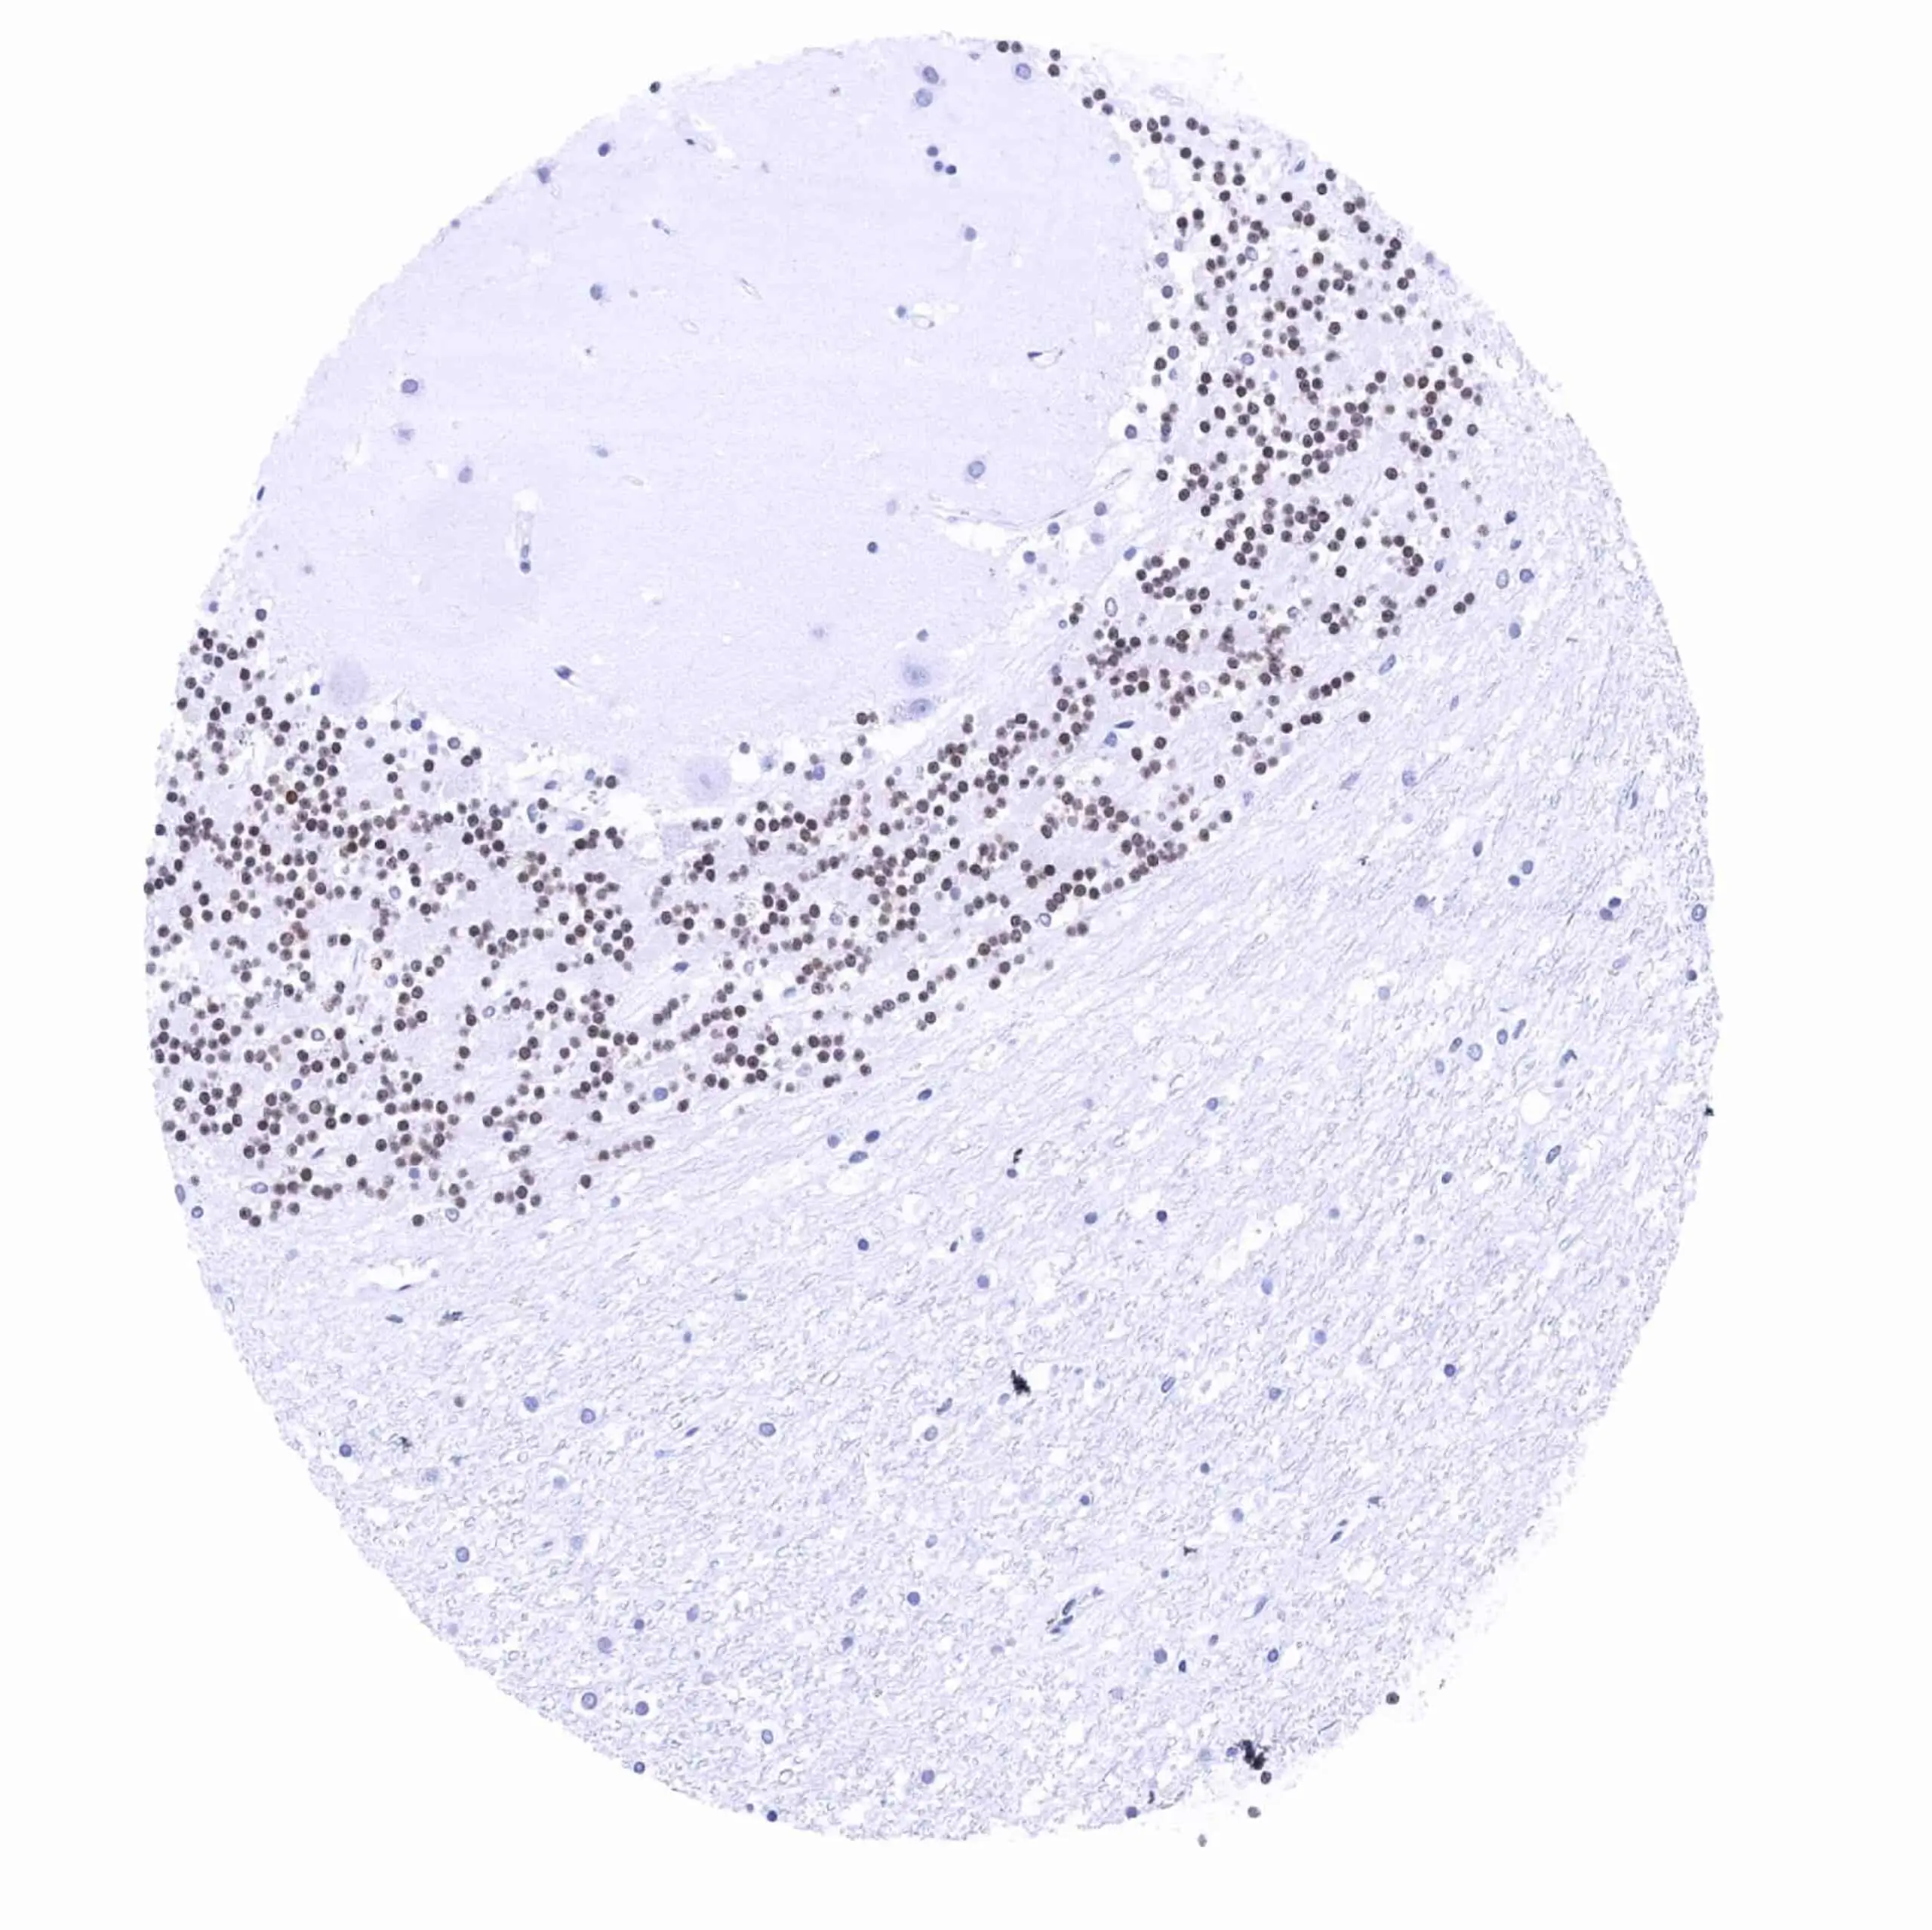

Anti-PAX6 antibody [MSVA-706M] HistoMAX™ used in IHC (Paraffin sections) (IHC-P). GTX04487

GTX04487 IHC-P Image

IHC-P analysis of human pancreas tissue using GTX04487 PAX6 antibody [MSVA-706M] HistoMAX™.

Pancreas with intense nuclear PAX6 staining of islet cells scaled.